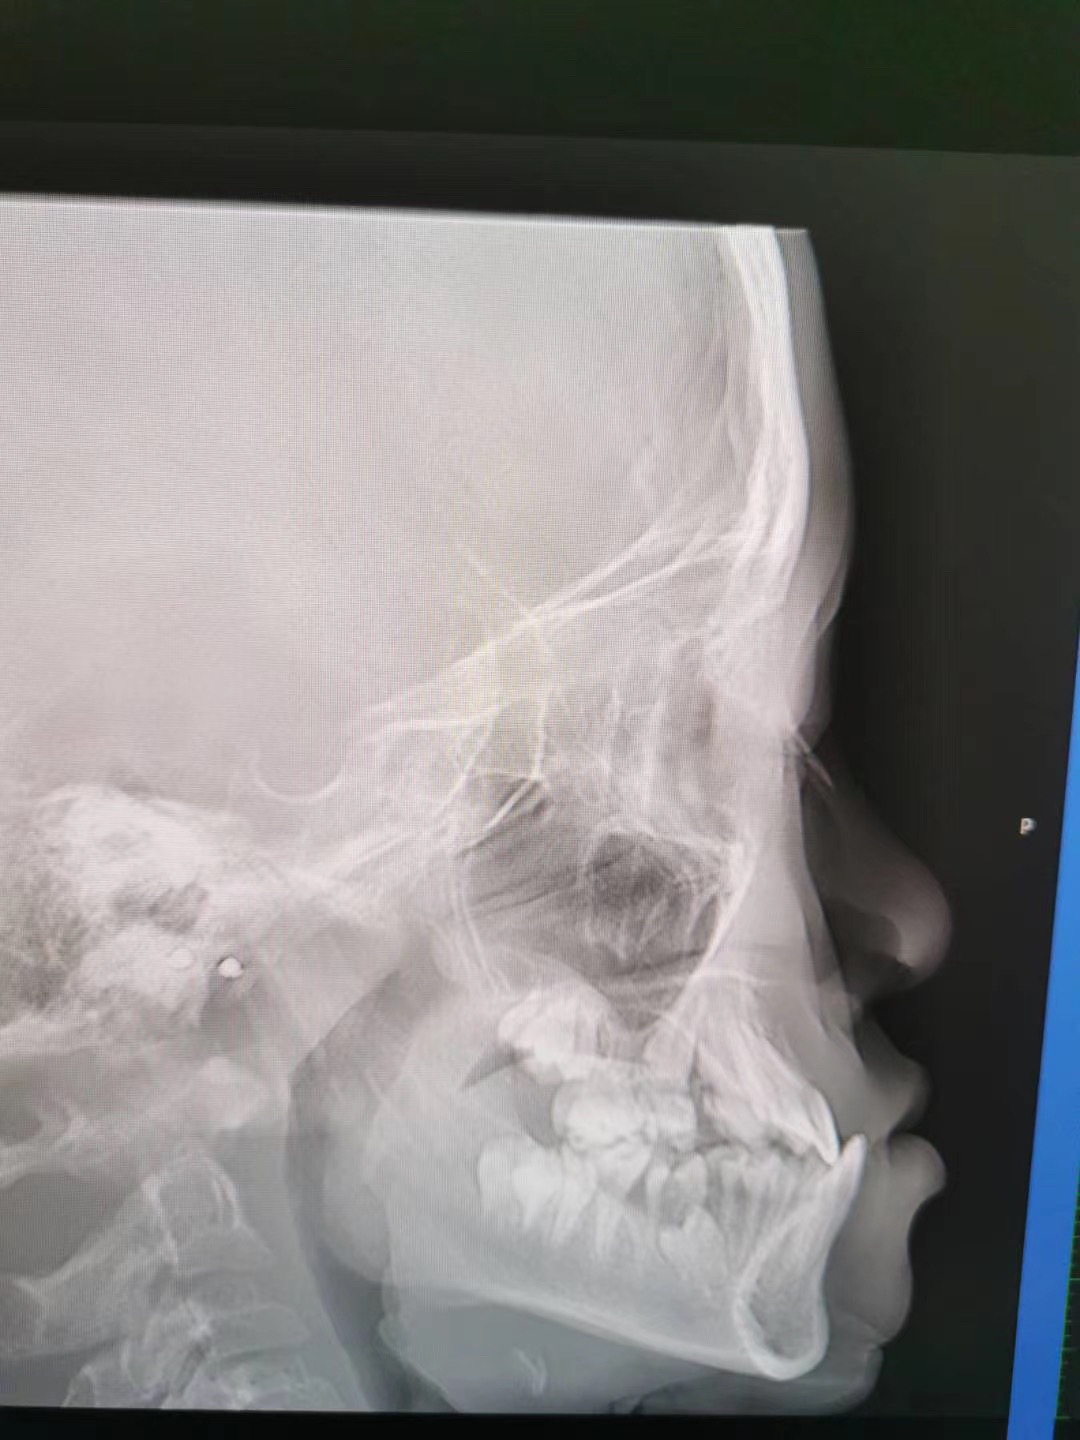

因为一下牙齿情况要早些干预,毕竟地包天这个牙齿情况,早发现,早干预,地包天矫正越早越好,当家长发现小孩子有地包天的趋势,就要及时咨询口腔医生,早期的时候可以通过活动矫正器简单的方法来预防和纠正不让他进一步的发展。有些小孩子乳牙期间就有地包天,家长不要以为没什么影响,一直拖延的话,会增加矫正的难度,其实有些牙齿情况会遗传的,就比如电视剧的情况,所以家长要及时注意哦!